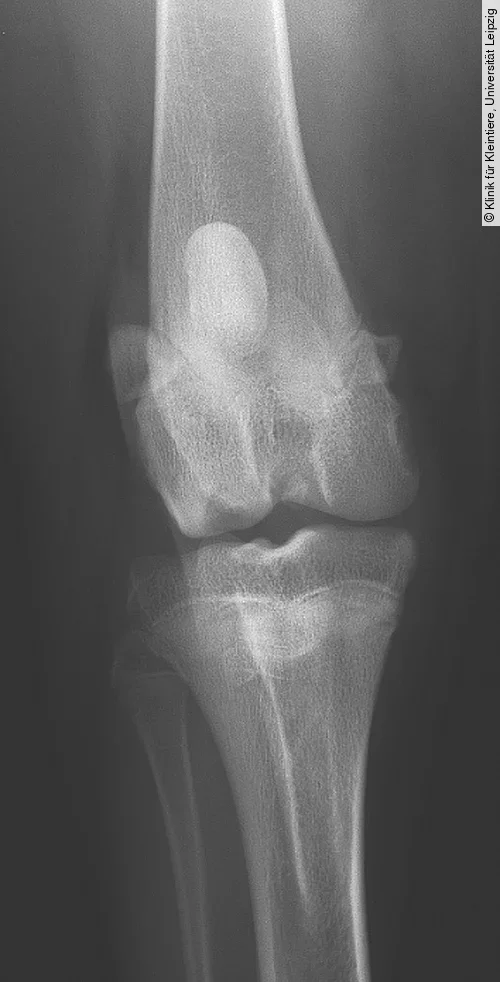

Für die Darstellung der OCD am lateralen und medialen Condylus femoris wird eine mediolaterale und eine kraniokaudale oder kaudokraniale Röntgenaufnahme benötigt. Obwohl die mediolaterale Aufnahme häufig schon pathognomonische Anzeichen der OCD zeigt, ist eine kraniokaudale oder kaudokraniale Projektion erforderlich, um festzustellen, welcher Kondylus betroffen ist [4].

Die Röntgenbilder können Veränderungen wie eine Abflachung der Gelenkoberfläche an einem der beiden Femurkondylen (meist Medialfläche lateraler Kondylus), einen konkaven Defekt am subchondralen Knochen (mit oder ohne angrenzende Sklerose) oder selten mineralisierte Knorpelschuppen zeigen (Abb. [ 6 ], Abb. [ 7 ]).

Differenzialdiagnostisch kann es zu einer Verwechslung der normalen Fossa extensoria (Ursprung M. extensor digitorum longus) mit einer OCD-Läsion kommen. Die Fossa resultiert aber im Gegensatz zur OCD-Läsion nicht in einem Defekt der Gelenkfläche (kraniokaudale Projektion) und ist auf der mediolateralen Aufnahme deutlich weiter kranial und proximal lokalisiert (Abb. [ 6 ]) [4], [22].